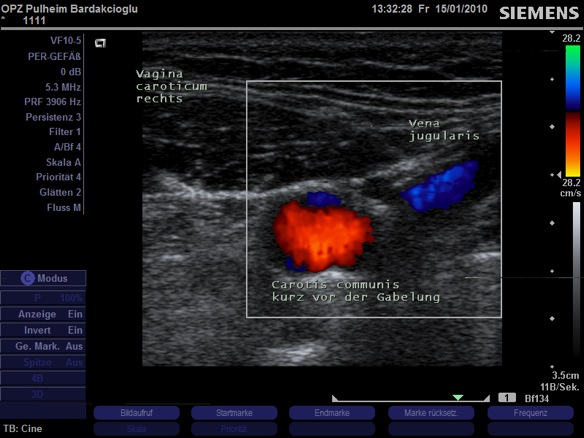

Pulheimer Gefäßzentrum

Neueste digitale Farbdoppler/Triplex-Sonographie für die sichere  Diagnostik, Therapie und Verlaufskontrolle

von Gefäßerkrankungen

Die hochauflösende farbcodierte Bildgebung erlaubt die vorzeitige Entdeckung gefährlicher Kalkablagerungen in Innenwänden der Gefäße. Diese Atherosklerotischen Plaques sind die Ursache für die häufisgsten lebensbedrohlichen Notfälle: Schlaganfall und Herzinfarkt.

Halsgefäße(Hirnversorgende Arterien)

Schlaganfallvorsorge

Abklärung von unklarer Synkope (Schwindelanfälle) und neurologischen Störungen

Verlaufskontrolle bei Carotis-Bypass-OPs